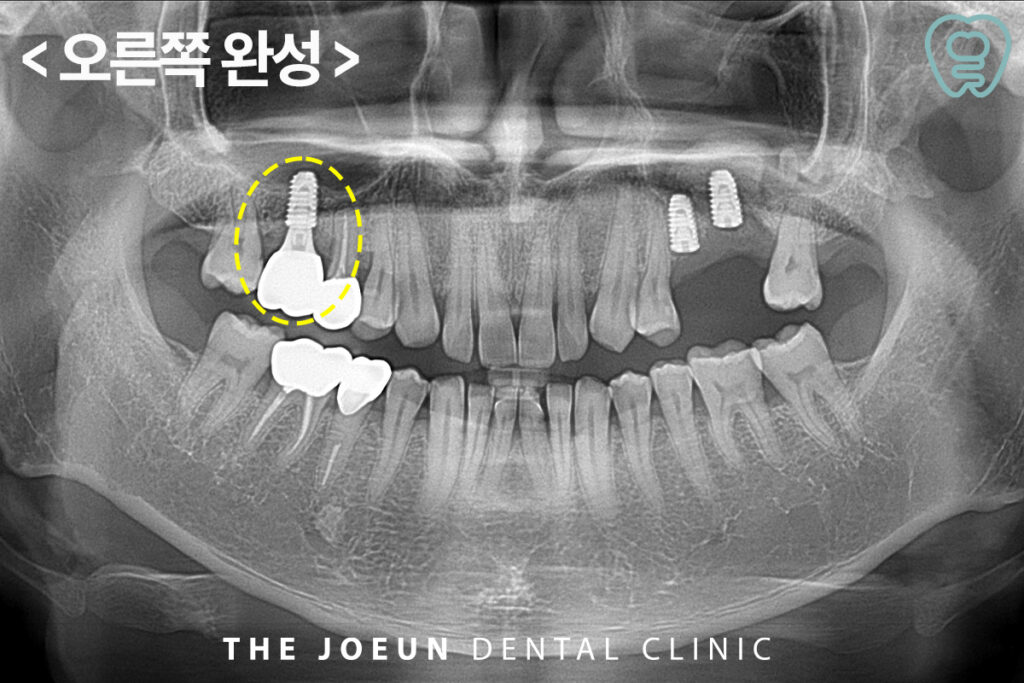

이후, 식립 3개월 만에 상대적으로 간단한 방법으로 뼈이식을 진행한 오른쪽부터 최종 보철물을 완성하였습니다.